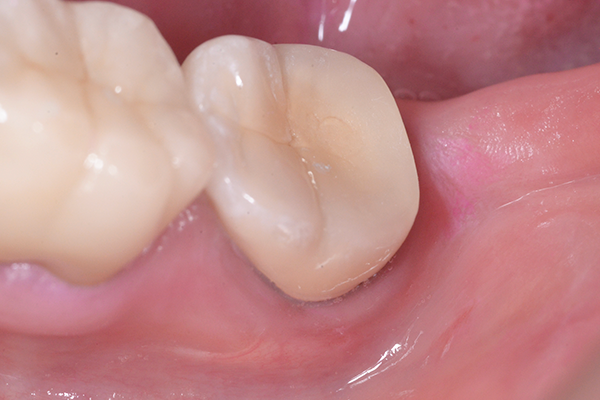

1.治療前

左下の歯が噛むと痛みがあると来院されました。

2.治療前のレントゲン

お口の中の診査と、レントゲンで一番後ろの歯が原因とわかり根の治療(感染根管治療)を開始します。